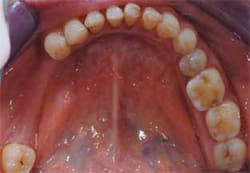

A 74-year-old woman presented to the Department of International Advanced Esthetic Dentistry Program at New York University College of Dentistry. Her chief complaint was the appearance of her teeth. She believed they were old, thin, dark, small, and spaced (Figure 1). She wanted her teeth to be whiter but natural and “normal” size without spaces. She reported no pain symptoms related to the TMJs, musculature, or other dental structures. Noticeable wear was present on the maxillary and mandibular anterior teeth and the remaining posterior natural teeth (Figure 2 and Figure 3). Vertical dimension was closed slightly, and centric occlusion and centric relation were coincidental. Ideally, all the posterior teeth would be restored and the vertical dimension increased in the posterior about 1 mm. This would result in a 3-mm anterior correction. However, financial constraints prohibited this.

Figure 1 Patient exhibited spacing, discolored teeth, and a reverse smile. | Figure 2 Occlusal view of the maxillary arch demonstrating wear, decay, and implants. | ||||||

Figure 3 Occlusal view of the mandibular arch demonstrating edentulous area and worn posterior teeth. | Figure 4 Patient presented with blunted gingival papilla, irregular gingival zenith, reverse smile, and an extruded right posterior segment. | ||||||